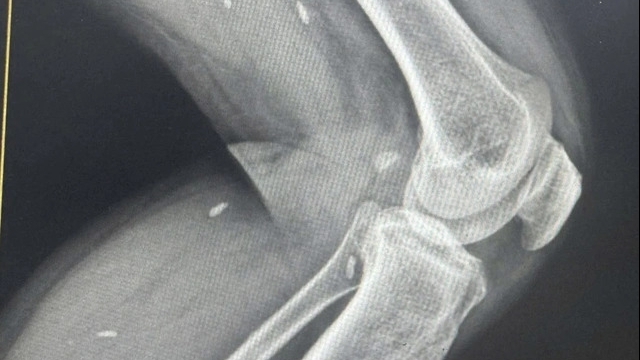

![]() |